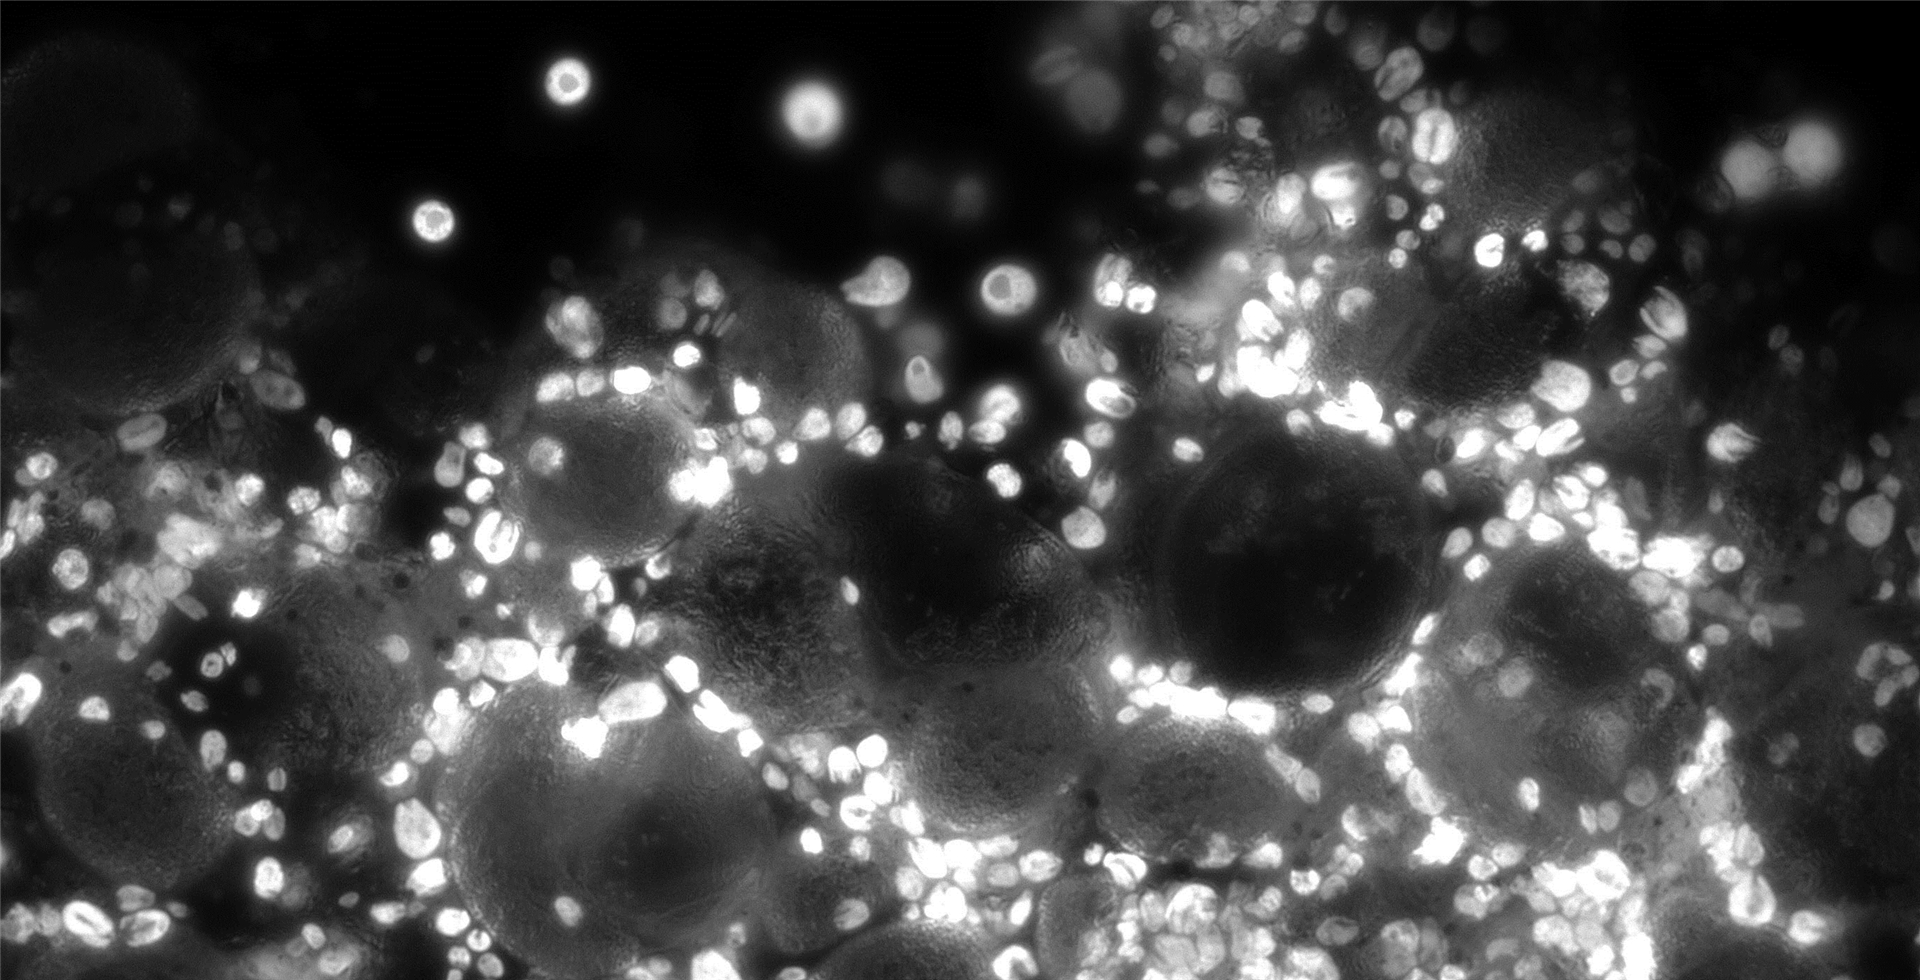

High Sensitivity NIR By Dhyana